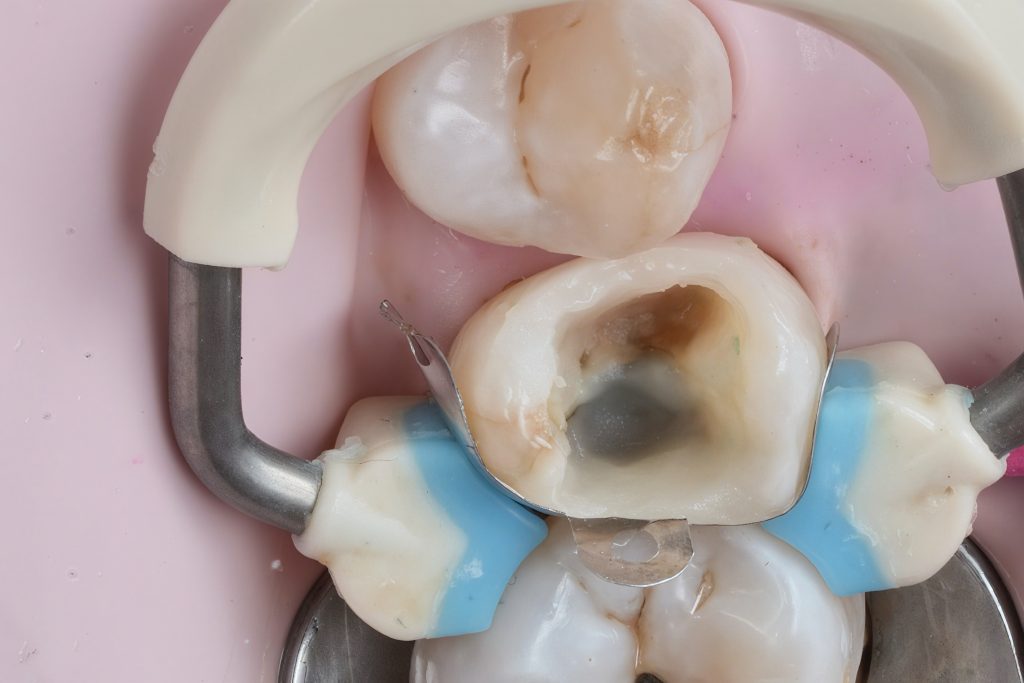

Rubber dam isolation achieved using clamp stabilization to maintain a dry and clean operative field – essential for adhesive dentistry (Fig 1–2).

2. Caries Removal & Margin Management

Defective composite and caries were removed in a controlled manner preserving sound enamel walls. Teflon floss ties and wooden wedges used for separation and gingival retraction (Fig 3–6).

- Preoperative occlusal view showing defective composite & caries

- Rubber dam isolation

- Initial caries exposure and removal

- Proximal clearance and wedge placement